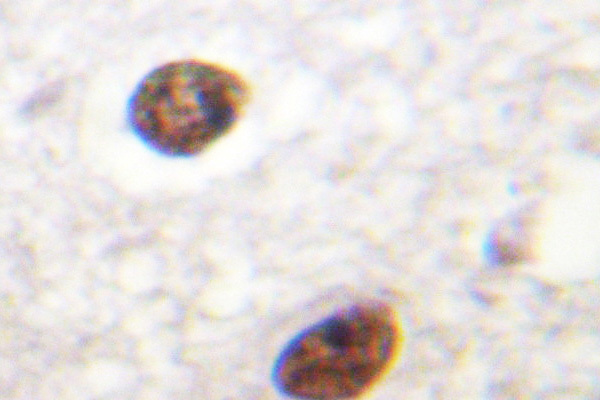

Supportive validation

- Submitted by

- OriGene (provider)

- Main image

- Experimental details

- Immunohistochemistry (IHC) analyzes of Histone H3.3 antibody in paraffin-embedded human brain tissue.

- Validation comment

- IHC